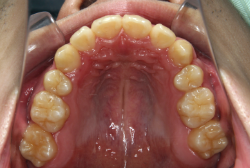

「歯並びの凸凹を直したい」という主訴で来院したケースです。診断の結果、たしかに「叢生」という隙間が足りないと言うことが原因の凸凹症例でした。

しかし、それ以上に問題なのは「前歯の噛み合い方が深すぎる」という症状で、初診の歯の正面写真を見ると下の前歯が全く見えません。こういう症状を矯正学では「過蓋咬合(かがいこうごう)」と言います。過蓋咬合を放置すると、将来的に顎関節に悪影響を与えるとされており、顎関節症の原因因子の一つです。また下の前歯の先端が、上の前歯の裏側の歯茎と強く接触するため、歯周病の原因にもなります。

検査の結果、凸凹が軽症なため非抜歯で矯正すること可能と判断、マルチブラケット装置にて治療しました。治療後は歯並びが綺麗になっただけでなく、噛み合わせ的にも正しい状態が確立しています。